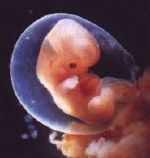

Diese scheinbar einfache Frage trotzt einer einfachen Antwort, weil es keine allgemein anerkannte Definition des Wortes Leben gibt. Von den Definitionen im Lexikon bietet eine - diejenige als,Merkmal, das einen lebendigen Körper von einem leblosen unterscheidet' - einen juristisch brauchbaren Ansatz. In den Vereinigten Staaten gilt ein Mensch im juristischen Sinne erst dann als tot, wenn die Hirnfunktion ausgesetzt hat, und nicht schon, wenn die Herzfunktion ausgesetzt hat. Daher könnte man sagen, das Leben beginnt erst dann, wenn sich im Embryo die Gehirnfunktionen herausbilden; das geschieht aber eher Wochen als Minuten, Stunden oder Tage nach der Befruchtung. Daher meine ich, dass ein eingefrorener zwei bis drei Tage alter Embryo, der noch nicht in die Gebärmutter einer Frau gelangt ist, noch nicht lebt.

Prof. Dr. Carl Djerassi, Chemie an der Stanford University in Palo Alto, Erfinder der Anti-Baby-Pille